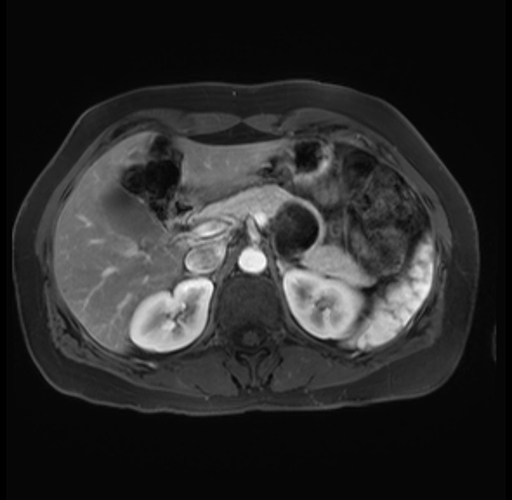

Imaging Analysis

Look through the patient's CT scan to identify any areas of concern for the necessary procedure.

Based on your CT findings, which issue(s) are present and would give reason for "planned slowing down moment(s)" in this case?

Considering a standard distal pancreatectomy procedure, what step(s) of the operation would you do differently in this case?